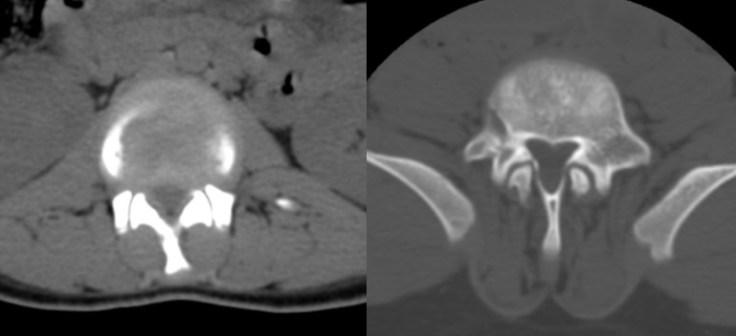

le canal cervical étroit de l’achondroplasie

il existe une étroitesse évolutive du canal cervical qui peut entraîner une compression médullaire et nécessiter une décompression par voie postérieure (laminoplastie). Cette compression se manifeste plus tard dans l’enfance et l’adolescence.

il existe également un rétrécissement du canal rachidien lombaire moyen et haut, avec compression de la moelle et des racines de la queue de cheval. Le canal lombaire étroit, est lié à la brièveté des pédicules et favorisé par l’hyperlordose lombaire avec épaississement réactionnel des ligaments jaunes. il survient à l’adolescence et l’âge adulte.